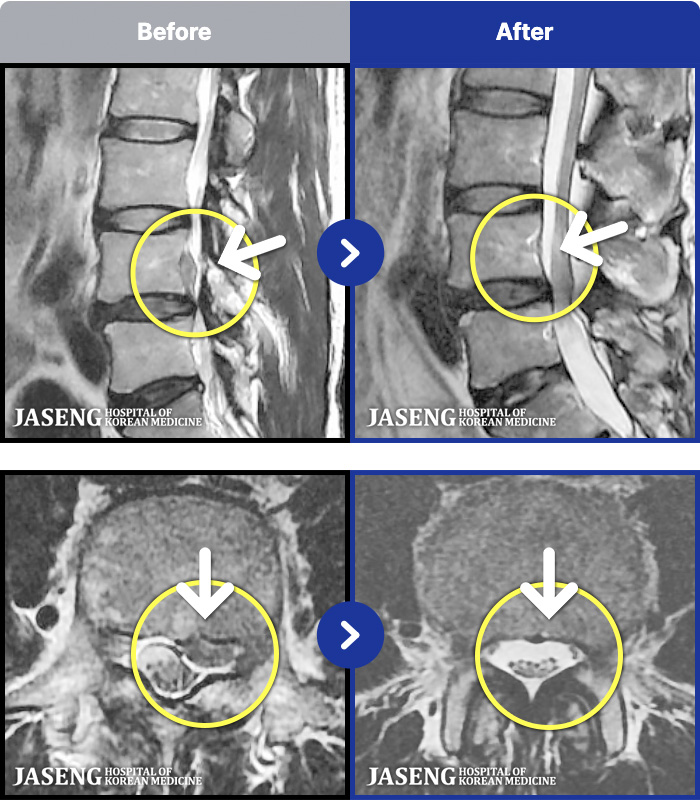

MRI ġ

1,304 MRI ũ ʸ Ȯϼ.